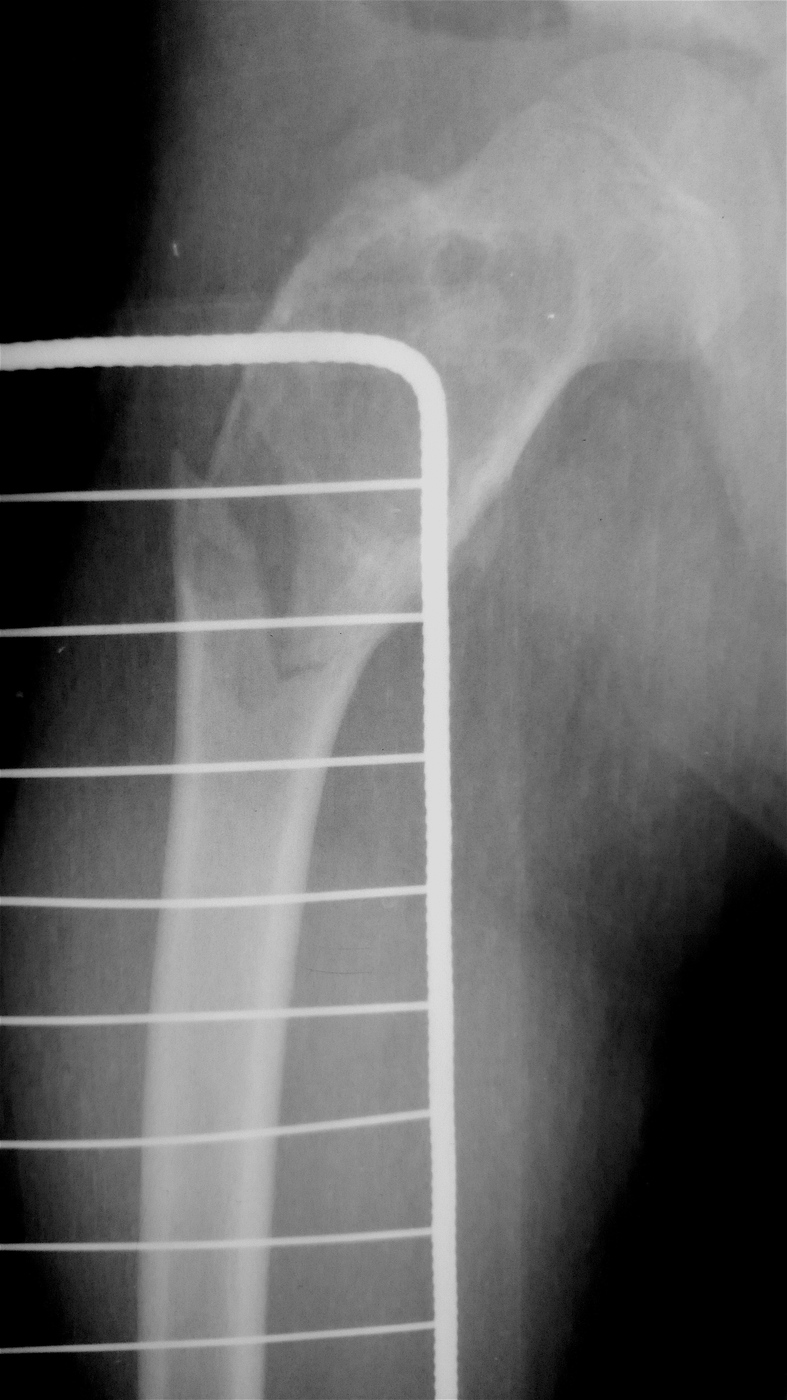

Выполнена резекция с аллопластикой губчатыми и кортикальными биоимплантатами "Лиопласт".